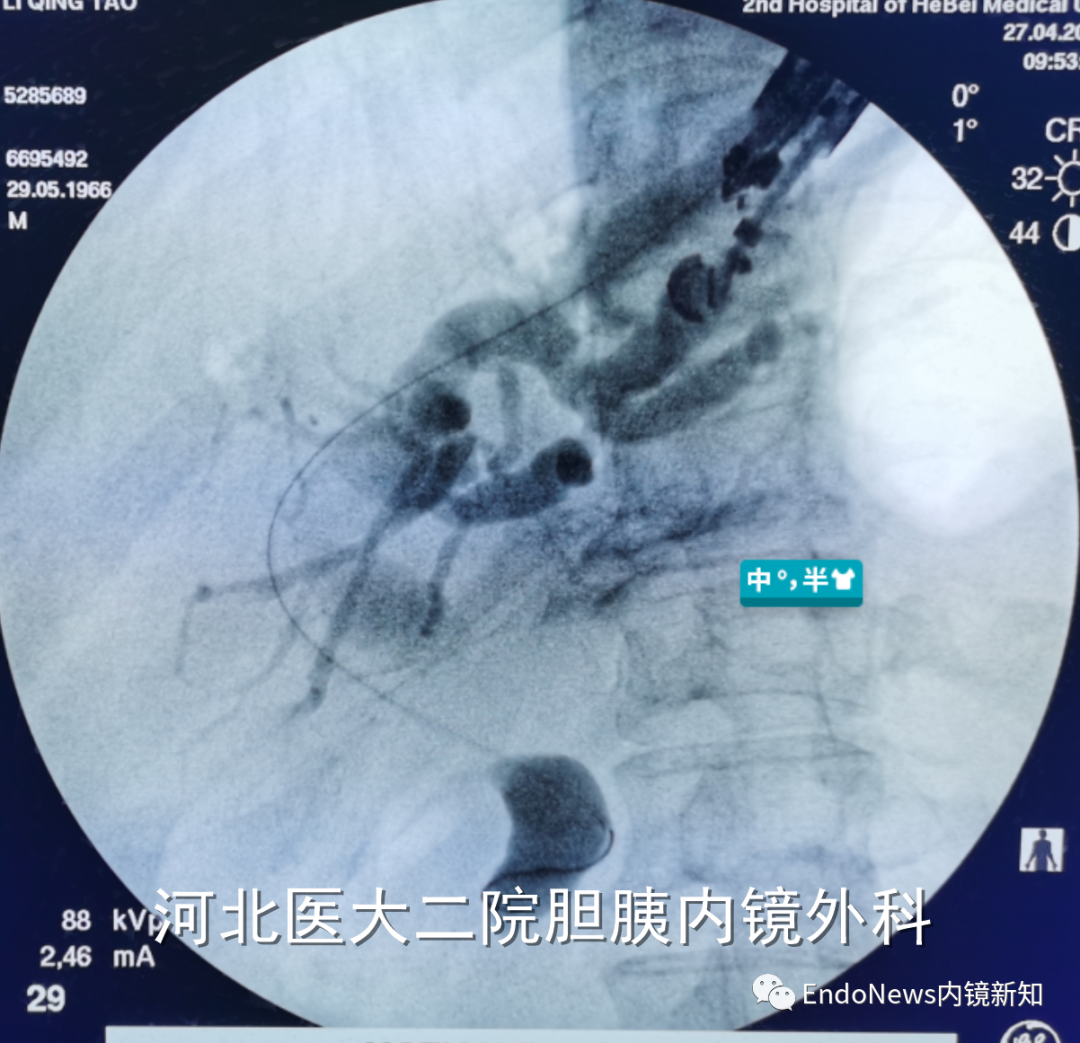

也有一些时候穿刺后导丝方向本身就是朝向胆总管下游方向的,比如下面两个病例:

如下图所示,肝门胆管狭窄(Bismuth IV型),导丝进入肝右叶胆管后就可以置入支架引流肝右叶胆管:

取石网篮 为什么贵EUS-BD操作中的细节:导丝如何超选?_https://www.jmylbn.com_新闻资讯_第14张